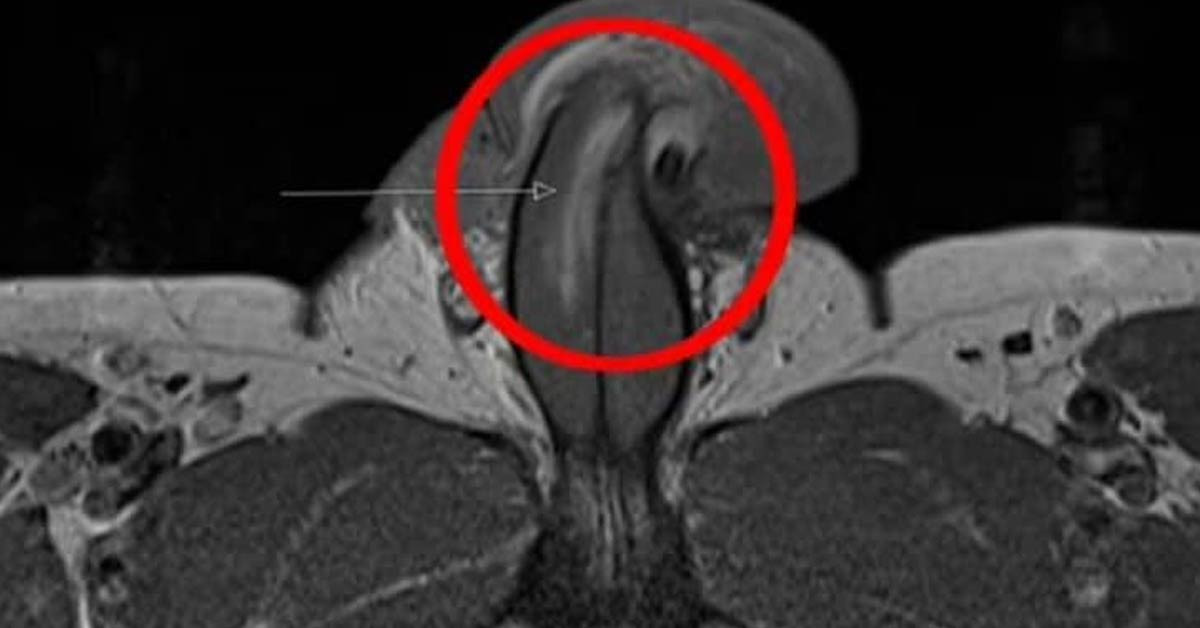

Dr Michael Guirguis yaptığı ilk müdahalenin sonunda adamın penis kırığı olduğunu sağ tunika albugineasının yırtıldığını dile getirdi.

Adam penisinin bükülmesini engellemek için, diğer taraftan kırılması ve düzeltilmesi için zorlu bir ameliyat geçirdi.

Dr. Michael Guirguis penisinin tamamen kırılması gerektiğini "aksi takdirde penis dik olmayacak ve düz olacak ve hastanın büyük olasılıkla istemeyeceği bir eğriliğe sahip olacak" sözleriyle anlattı.